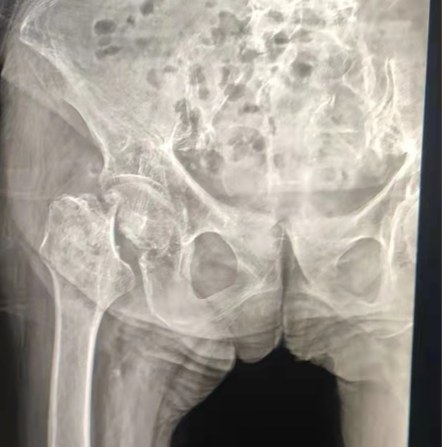

Vaka paylaşımı | 70 yaşında bir hasta, lepu çimentolu kalça sistemi ile toplam kalça değiştirme aldı

Çimentolu kalça sistemi: